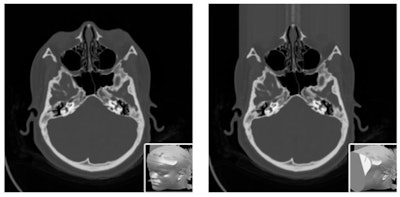

Patients also need to know their images are properly anonymized, he continued. "We know that with today's facial recognition, it is easy for a computer to match a reconstructed image from a CT or MR image of your head to a picture that you published on WhatsApp or the internet."

To avoid such risks, facial data from medical images can be blurred out, but this prevents studies on the nose, eyes, or sinuses to be performed on such altered data. Some data security experts recommend removing all identifying features, including blurring out tattoos on CT scans of the skin, for example. Ratib wonders how much each patient should be informed about what measures are being taken to protect the confidentiality of data.